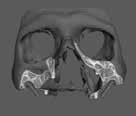

A maradó fogak gyökérreszorpciója patológiás folyamat. Az elváltozások elhelyezkedése alapján csoportosíthatjuk őket külső és belső reszorpciós folyamatokra. A külső gyökérreszorpciók egyre gyakrabban diagnosztizált formája a külső nyaki reszorpció (angolul External Cervical Resorption, ECR) [1. és 2. kép]. Az ECR egy komplex elváltozás, amely egyszerre érintheti a fog keményszöveti állományát, a parodontális szöveteket és előrehaladott esetben a pulpaszövetet is. A modern diagnosztikai eszközöknek köszönhetően egyre gyakrabban és egyre korábban kerül diagnosztizálásra ez a típusú lézió, így a kezelése is egyre inkább a mindennapi klinikum részévé válik az endodonciával foglalkozó kollégák számára. A 3 dimenziós diagnosztikai eszközök terjedésével felmerült az igény egy 3 dimenziós klasszifikációra. Patel és munkatársai 2018-ban kidolgoztak egy új klasszifikációt, amely segít az elváltozások kategorizálásában és a kezelések tervezésében [1]. A téma aktualitását jól mutatja, hogy ezzel egy időben az ESE (European Society of Endodontology) is kidolgozott egy állásfoglalást a külső nyaki reszorpciók diagnosztikájával és terápiás lehetőségeivel kapcsolatban [2].

1. és 2. kép: Külső nyaki reszorpciós elváltozások CBCT képen.Kónuszos felépítmény kapcsolat